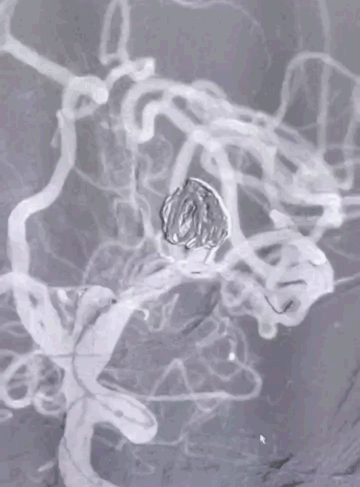

Tubridge Case 2